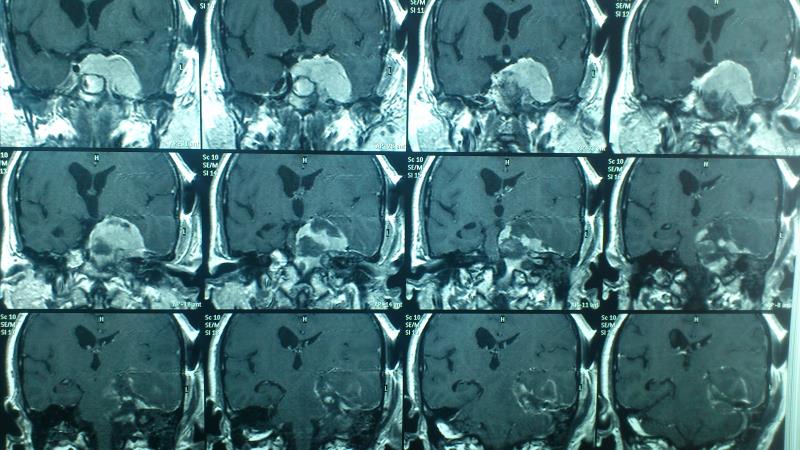

Ασθενής γυναίκα ηλικίας 56 ετών προσήλθε λόγω αστάθειας βάδισης, έκπτωσης ακουστικής οξύτητας αριστερά, αιμωδιών προσώπου κατανομής V2-V3 αριστερά και διπλωπίας ( ήπια πάρεση κοινού κινητικού ) . Ο προεγχειρητικός απεικονιστικός με μαγνητική τομογραφία εγκεφάλου ανέδειξε εικόνα συμβατή με μηνιγγίωμα αποκλίματος και λιθοειδούς ( petroclival ) , με επέκταση στο Meckel's cave και στον αριστερό σηραγγώδη κόλπο καθ' όλη την έκτασή του. Λόγω μεγάλου μεγέθους και έκτασης του μηνιγγιώματος αποφασίστηκε η αφαίρεσή του σε 2 στάδια. H προεγχειρητική αγγειογραφία ανέδειξε  υπολειπόμενο τον αριστερό εγκάρσιο κόλπο με έντονο παράπλευρο δίκτυο  με δυνατότητα εκτομής  του (transsinus ), αποφεύγοντας τις διαλιθοειδικές προσπελάσεις και την συνοδό νοσηρότητά τους. Η ασθενής είχε ομαλή μετεγχειρητική πορεία με βελτίωση της αστάθειας βάδισης και της ακουστικής οξύτητας. Ο μετεγχειρητικός απεικονιστικός έλεγχος ανέδειξε αφαίρεση του τμήματος του όγκου στον οπίσθιο κρανιακό βόθρο.

Προεγχειρητικός απεικονιστικός έλεγχος